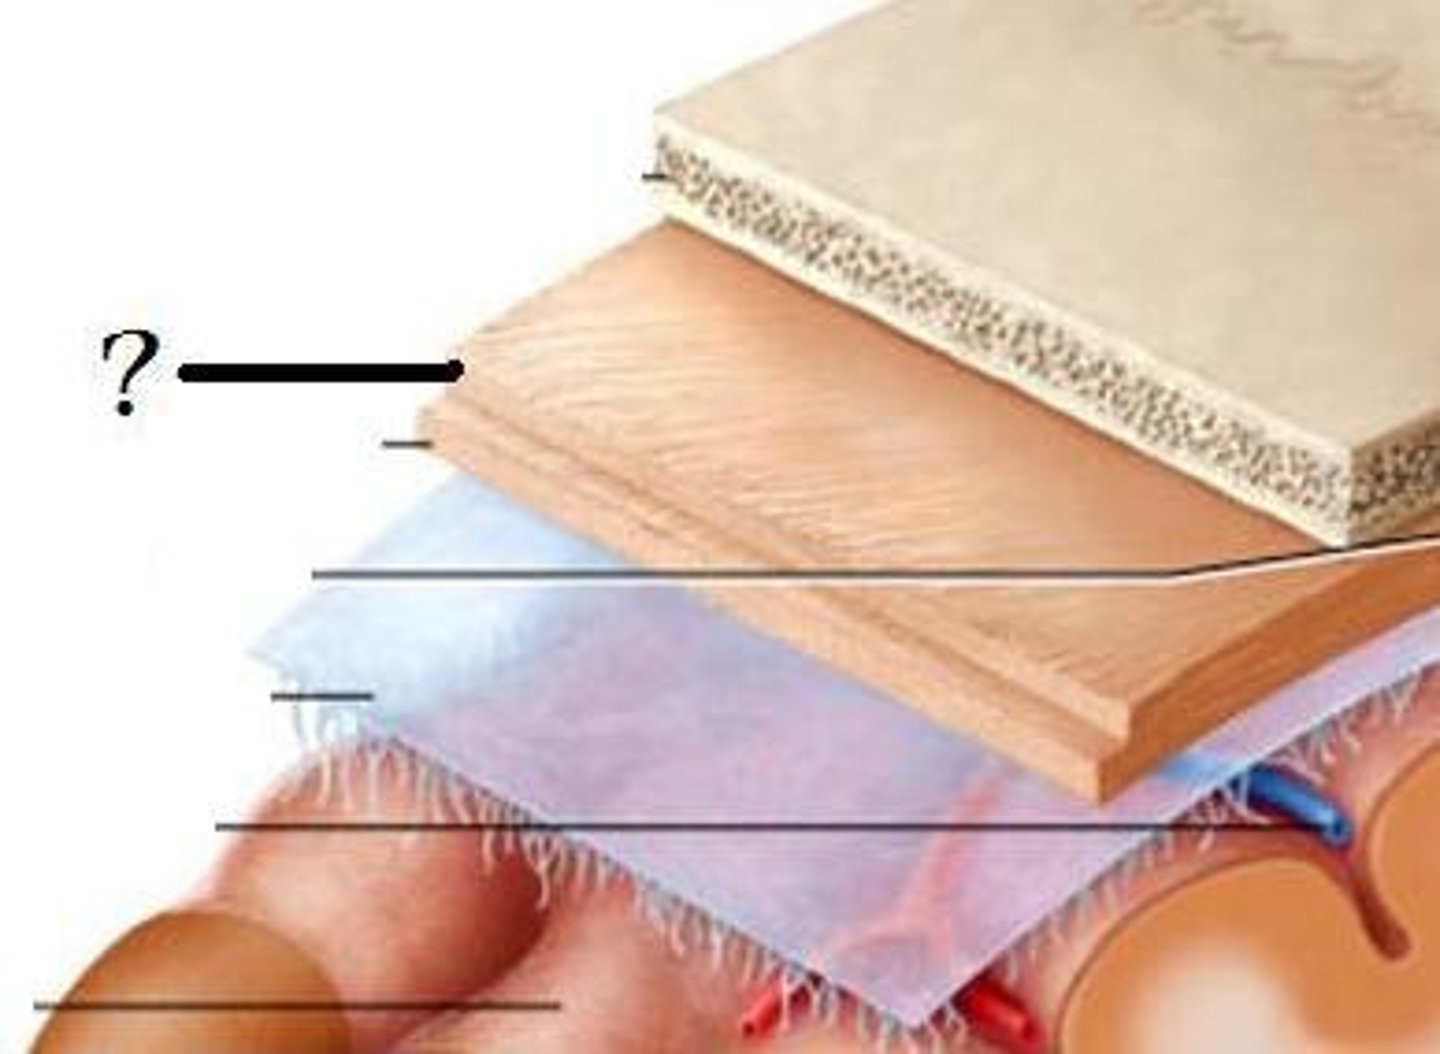

Meninges

-Three connective tissue membranes that envelope the CNS

-Protect the CNS and provide structural framework for its arteries and veins

Meninges Location

-Lies between the nervous tissue and bone

Cranial dura mater

-Outer periosteal

-Inner meningeal

-Folds inward to extend between parts of the brain

Cranial dura mater location

-Layers separated by dural sinuses

-Pressed closely against cranial bones

=No epidural space

=Only attached to bone around foramen magnum, stella turcica, crista galli, and sutures of the skull

Periosteal

-Equivalent to periosteum of cranial bones

Meningeal

-Continuous into vertebral canal and forms dural sheath around spinal cord

Dural sinuses

-Separates layers of cranial dura mater

-Collect blood circulating though brain

Arachnoid mater

-Transparent membrane over brain surface

Subarachnoid space

-Separates arachnoid mater from pia mater below

-Contains CSF

Subdural space

-Separates arachnoid from dura mater above in some spaces

Pia mater

-Very thin membrane that follows contours of brain, even dipping into sulci

-Not usually visible without a microscope